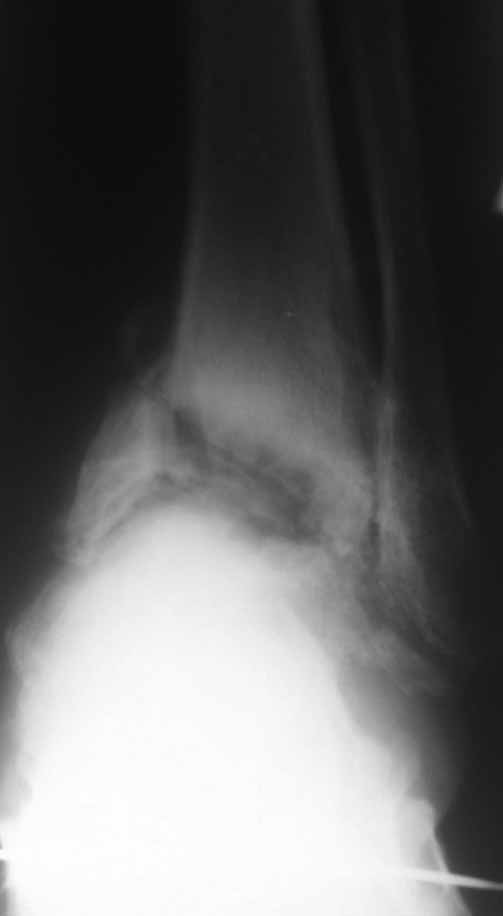

Да, вспомнил, была у нас такая пациентка. 20 с небольшим лет. СД 1 типа, тяжёлое течение, с 5 лет. Осложнения почти все, какие только могут быть - нефропатия, ХПН, ретинопатия, ангионевропатия, анемия 3 ст. и т.п. В анамнезе - кататравма. Оперировали в 2006, 2007 г., выполнялся панартродез на обеих стопах. В последующем всё плохо: неоднократные странные нагноения (после дренирования и 5 дней антибиотиков всё успокаивалось - до очередного обострения; при этом болевой синдром практически отсутствовал). Лечение сложное и дорогостоящее, вплоть до применения эритропоэтинов и т.п. Однако положение стоп сохранялось достаточно приличное, ходьба в ортезах. В 2009 г. появились жалобы на боли в других суставах. При обследовании (сцинтиграфии) были выявлены множественные очаги по всему организму, вплоть до деструкции головки плечевой кости (накопление РФП 200 - 1400%). Содержание свободных лёгких каппа-цепей 149,0 мкг/мл (норма 3,0 – 8,0 мкг/мл), лямбда-цепей 1,3 мкг/мл (норма 0,001 – 0,04 мкг/мл). Множественные повторные биопсии, трепанбиопсии и гистологии. Диф. диагностика с гематологическими заболеваниями, миеломной болезнью, амилоидозом (кстати, тогда я понял, что амилоидоз - это не совсем то, чему нас учили в своё время).

Головку плеча позже резецировали в другом стационаре. Больную видел этим летом, ходит всё также в ортезах (фиксаторы ГСС с боковыми шинками). Про остальное не спрашивайте.